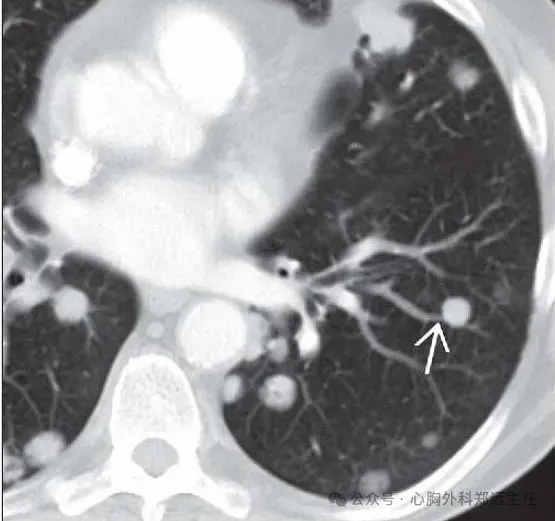

吸入有机粉尘同样也可引发肺结节的形成,例如采棉工人的棉尘肺、吸入谷物粉尘的农民肺以及暴露于木尘的木工等。下图是一位采棉女工,长期吸入植物性粉尘,在肺里形成很多微结节和索条状影。